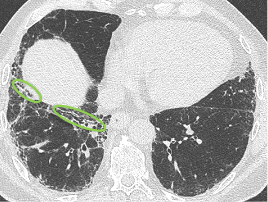

Der behandelnde Arzt hat sich für eine hochauflösende Computertomographie

(HRCT) des Thorax entschieden und folgende klinische Befundung erhoben:

Befundung des HRCT-Scans:

- Retikuläre Veränderungen

- Milchglasartige Dichteanhebungen

- Traktionsbronchiektasen

- Nicht vorhanden: Honigwabenmuster

CT: Computertomographie | HRCT: hochauflösende Computertomographie